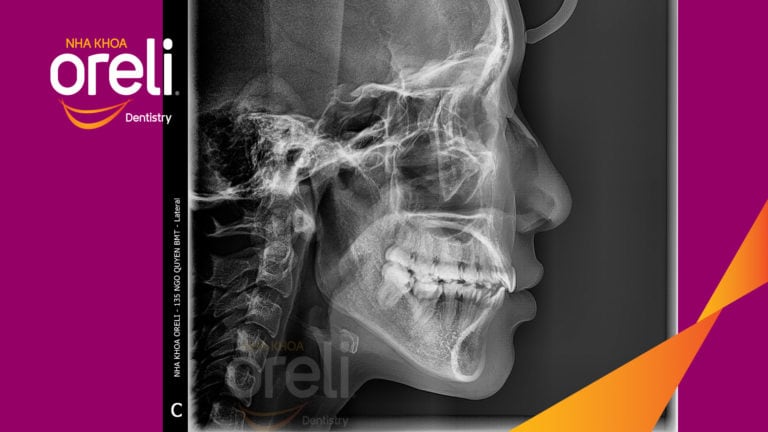

Ca niềng răng đặc biệt: kéo răng 7, 8 thay thế 3 răng 6 bị hư tại Oreli Niềng răngDi gần răng 7 8 Xem thêm